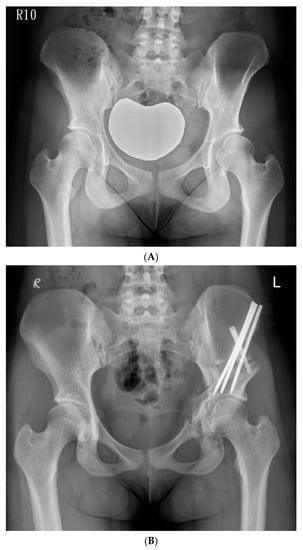

The hip was flexed and adducted to relax the medial soft tissues, and the osteotomy was made through the medial cortex. The osteotomy was extended from the posterior end of the iliac saw-cut and passed over the iliopectineal line, through the medial quadrilateral plate, and parallel to the anterior edge of the sciatic notch as observed through iliac oblique fluoroscopy, and was subsequently directed towards the ischial spine. We used a 30° angled, long-handled chisel to connect the anterior and posterior ischial cuts to complete the osteotomy of the posteroinferomedial corner of the quadrilateral plate. We used a bone clamp as a joystick to manipulate the periacetabular bone by lifting the acetabular fragment slightly towards the ceiling, creating an initial displacement, followed by a three-step movement of lateral, distal, and internal rotation. We inserted the artificial bone graft substitutes into the osteotomy site with multiple 6.0-mm cannulated screws and fixed the ASIS with a 4.5-mm cannulated screw augmented with a transosseous suture. A 1/8” hemovac drain was inserted, and the wound was then closed by layers. (Figure 3A,B).

Figure 3.

(A) Preoperative anteroposterior standing radiograph of a 19-year-old woman who underwent Ganz Osteotomy for symptomatic left hip dysplasia. (B) Postoperative anteroposterior standing radiograph showed good coverage of the femoral head.